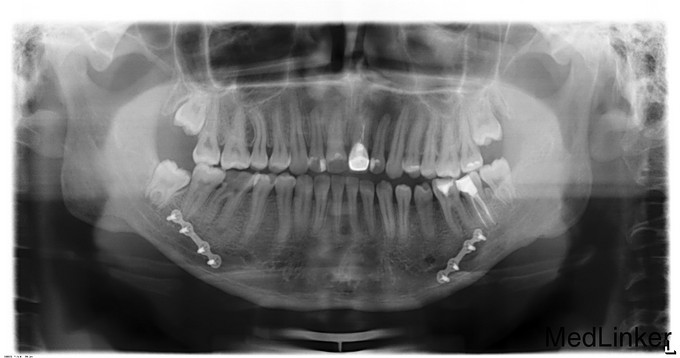

正颌术后半年要求取出钛板

诊断:1.双侧下颌正颌术后钛板存留2.36、46残冠,全麻下行双侧下颌骨钛板取出术+双侧下颌骨邻近瓣转移修复术+36、46拔除术,手术经过顺利,麻醉满意,术后予消炎、消肿等对症治疗。